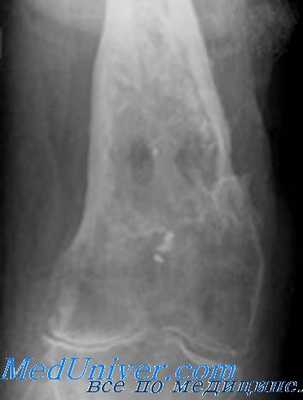

КТ стопы. Посттравматический хронический остеомиелит пяточной кости с наличием секвестра (красная стрелка) и свищевого хода (синяя стрелка).